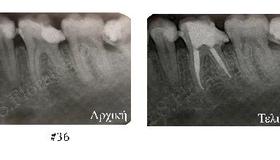

Ενδοδοντική Θεραπεία/Απονεύρωση